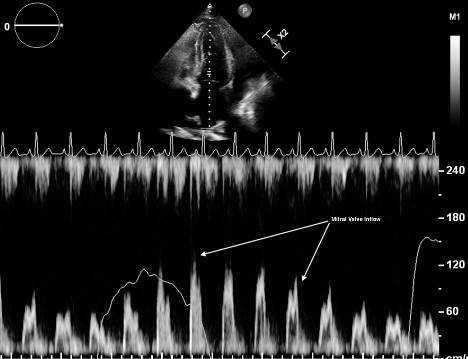

There are two methods to establish systolic/diastolic collapse. First, one can record a video clip in either the apical four-chamber view or subxiphoid view and rewind slowly to look at the chambers when the mitral valve is open (diastole) or closed (systole). Second, one can place the M mode marker over the anterior leaflet of the mitral valve to produce the image below (Figure 2). The mitral valve tracing produces an E and A wave during mitral opening, and thus ventricular diastole. Ventricular wall collapse during this peak establishes tamponade.5-8

Figure 2: M Mode tracing of mitral valve demonstrating diastolic right ventricular collapse. Image courtesy of Dr. Sarah Murthi.